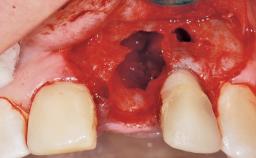

Late Flapless Placement of an Implant in a Maxillary Left Central Incisor Site

A 39-year-old male patient presented with a chief complaint of discomfort and gingival discoloration around his maxillary left central incisor. He was in good general health and was a non-smoker. His past dental history was significant because of the traumatic fracture of tooth 21 in a sporting accident at age 13. Initial dental treatment included endodontic therapy and a full-coverage restoration. The patient became symptomatic 5 years later, when structural failure of the tooth resulted in the dislodgment of the crown. Endodontic retreatment, apical surgery, and post-and-core restoration were performed.

Bone Volume Deficient horizontally, requiring prior grafting

Bone Augmentation Horizontal|Staged